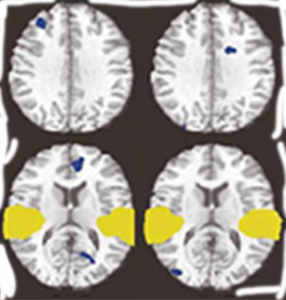

마음챙김 초보자(일반인)

휴식중

마음챙김중

마음챙김 수행자

1968년, 마음챙김의 효과를 과학적으로 검증하기 위한 연구가 8주간의 수련을 통해 진행되었으며, 그 결과 대뇌피질 좌측 전두엽의 활성 증가가 확인되었습니다. 연구에서는 스트레스로 인한 교감신경계의 과잉 활성은 완화되고, 안정 상태를 조절하는 부교감신경계의 기능이 상대적으로 우세해지는 변화가 관찰되었습니다. 특히, 마음챙김 수행자의 전두엽 활성 수준은 일반인보다 높게 나타났습니다. 이러한 연구 결과를 바탕으로, 1975년 하버드 의과대학에서는 일반인을 대상으로 한 마음챙김 치료법 「이완반응」을 도입하였습니다.